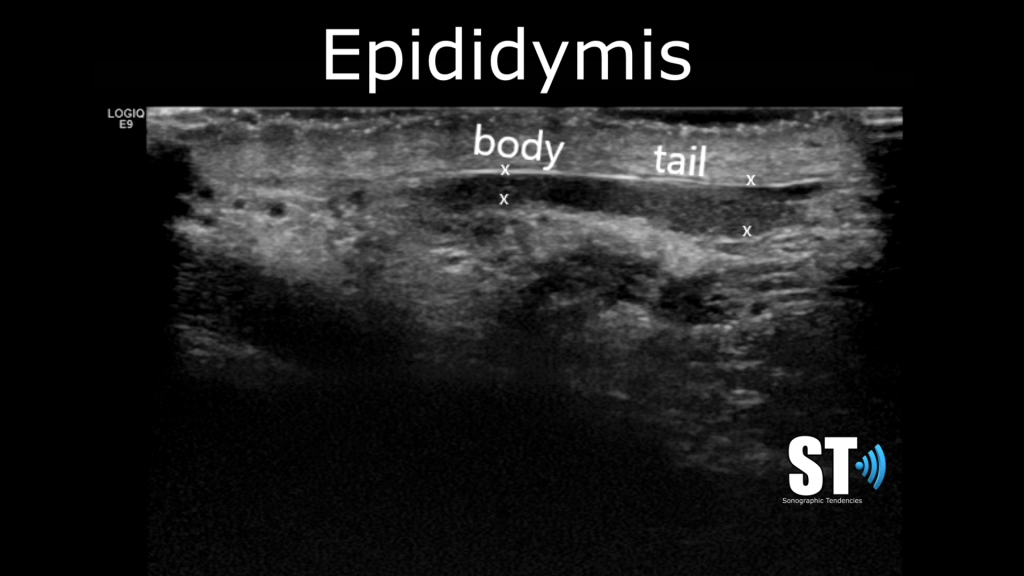

Epididymis

In sagittal image the epididymis, check for homogeneity, and look out for epididymal cysts and spermatoceles. Depending on your institution you may or may not have to measure the dimensions of the epididymis. Take images with color doppler. In cases of epididymitis there will be enlargement, hyperemia and fat edema.